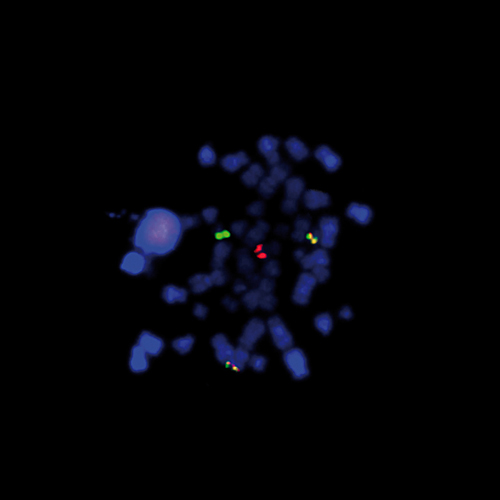

Prostate carcinoma: immunohistochemical staining of Galectin-3. Note the staining in the neoplastic cells and some staining in the stroma. Galectin-3: clone 9C4